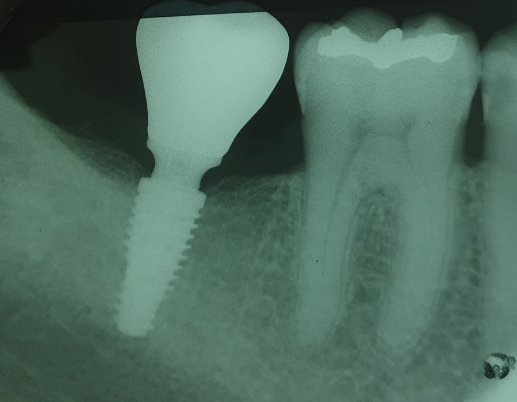

BIÓPSIAS,

TERCEIROS MOLARES

E IMPLANTODONTIA